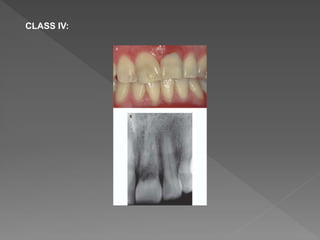

CLASS IV:

 Heithersay concluded that classes 1–3 were treatable, but class

4 lesions were not amenable to treatment, and these cases

would have benefited from alternative treatment such as

extraction and replacement with an implant retained crown